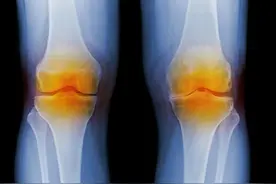

骨关节炎是一种慢性疾病,也是退行性病变,由诸多因素引起的,但根据局部因素和全身因素,把骨关节炎分为了原发性和继发性两大类。不管是哪种类型的骨关节炎疾病,都严重的影响了患者的生活,甚至导致了关节的残疾。那么,治疗骨性关节炎的方法是什么?

人们一提到骨关节炎就想到的是骨关节上出现了“炎症”,那么“炎症”如何处理呢?当然是“消炎”了!曾经就有不少患者问过我“骨关节炎能不能用阿莫西林来消炎呢?”“我能不能吃点头孢呢?”下面就给大家谈一谈骨关节炎的“消炎”问题。一、炎症是什么?